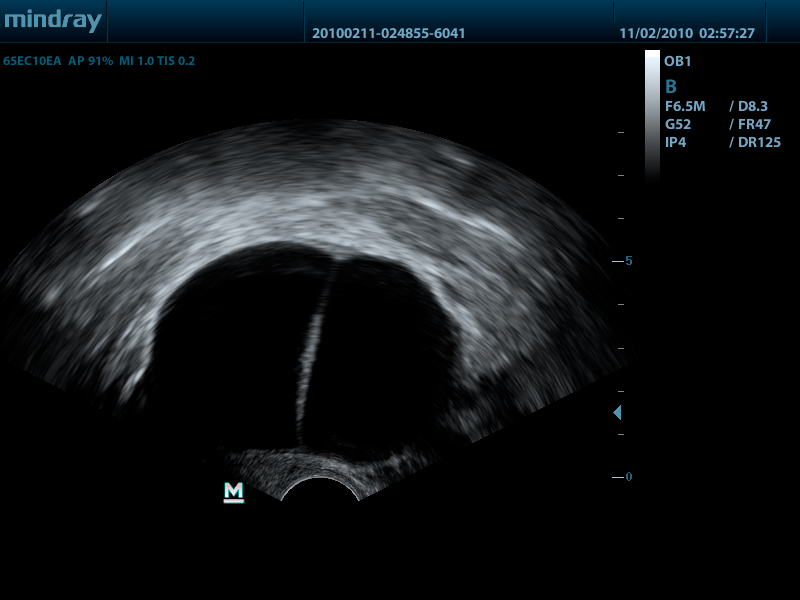

Внутриполостной датчик 65EC10EA (5.0/6.5/7.5/8.5/Н8.0/Н9.0 МГц, R-10 )